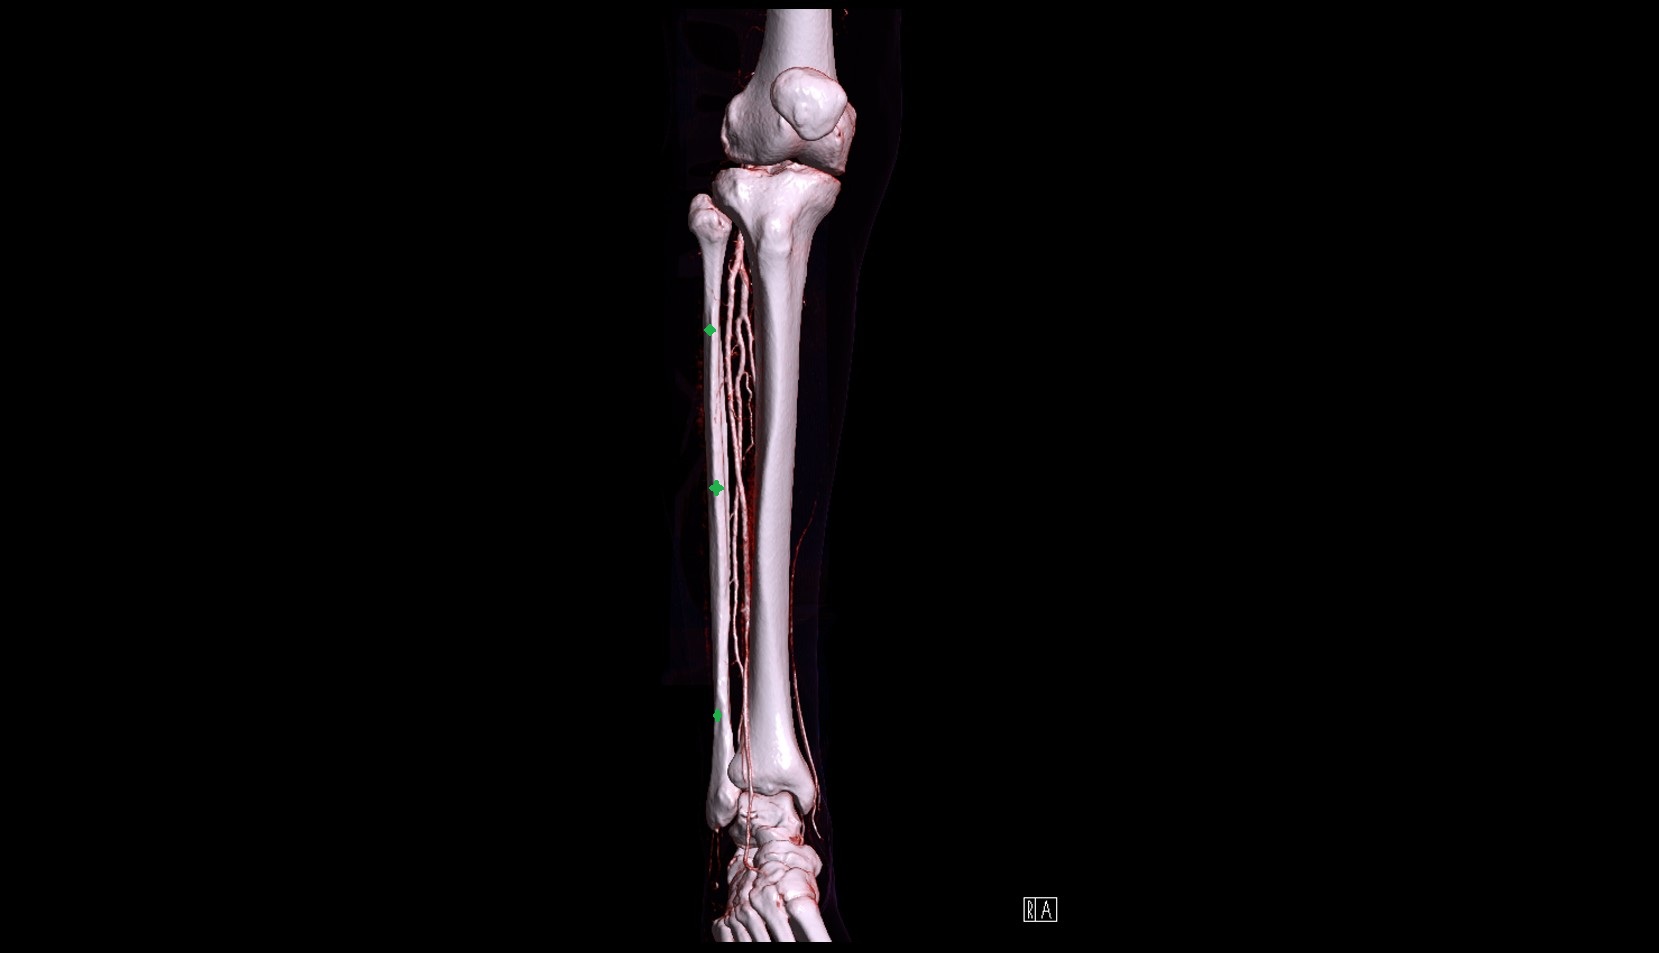

- Body of tibia

- Tibia

- Fibula

- Anterior tibial artery

- Fibular artery

- Posterior tibial artery